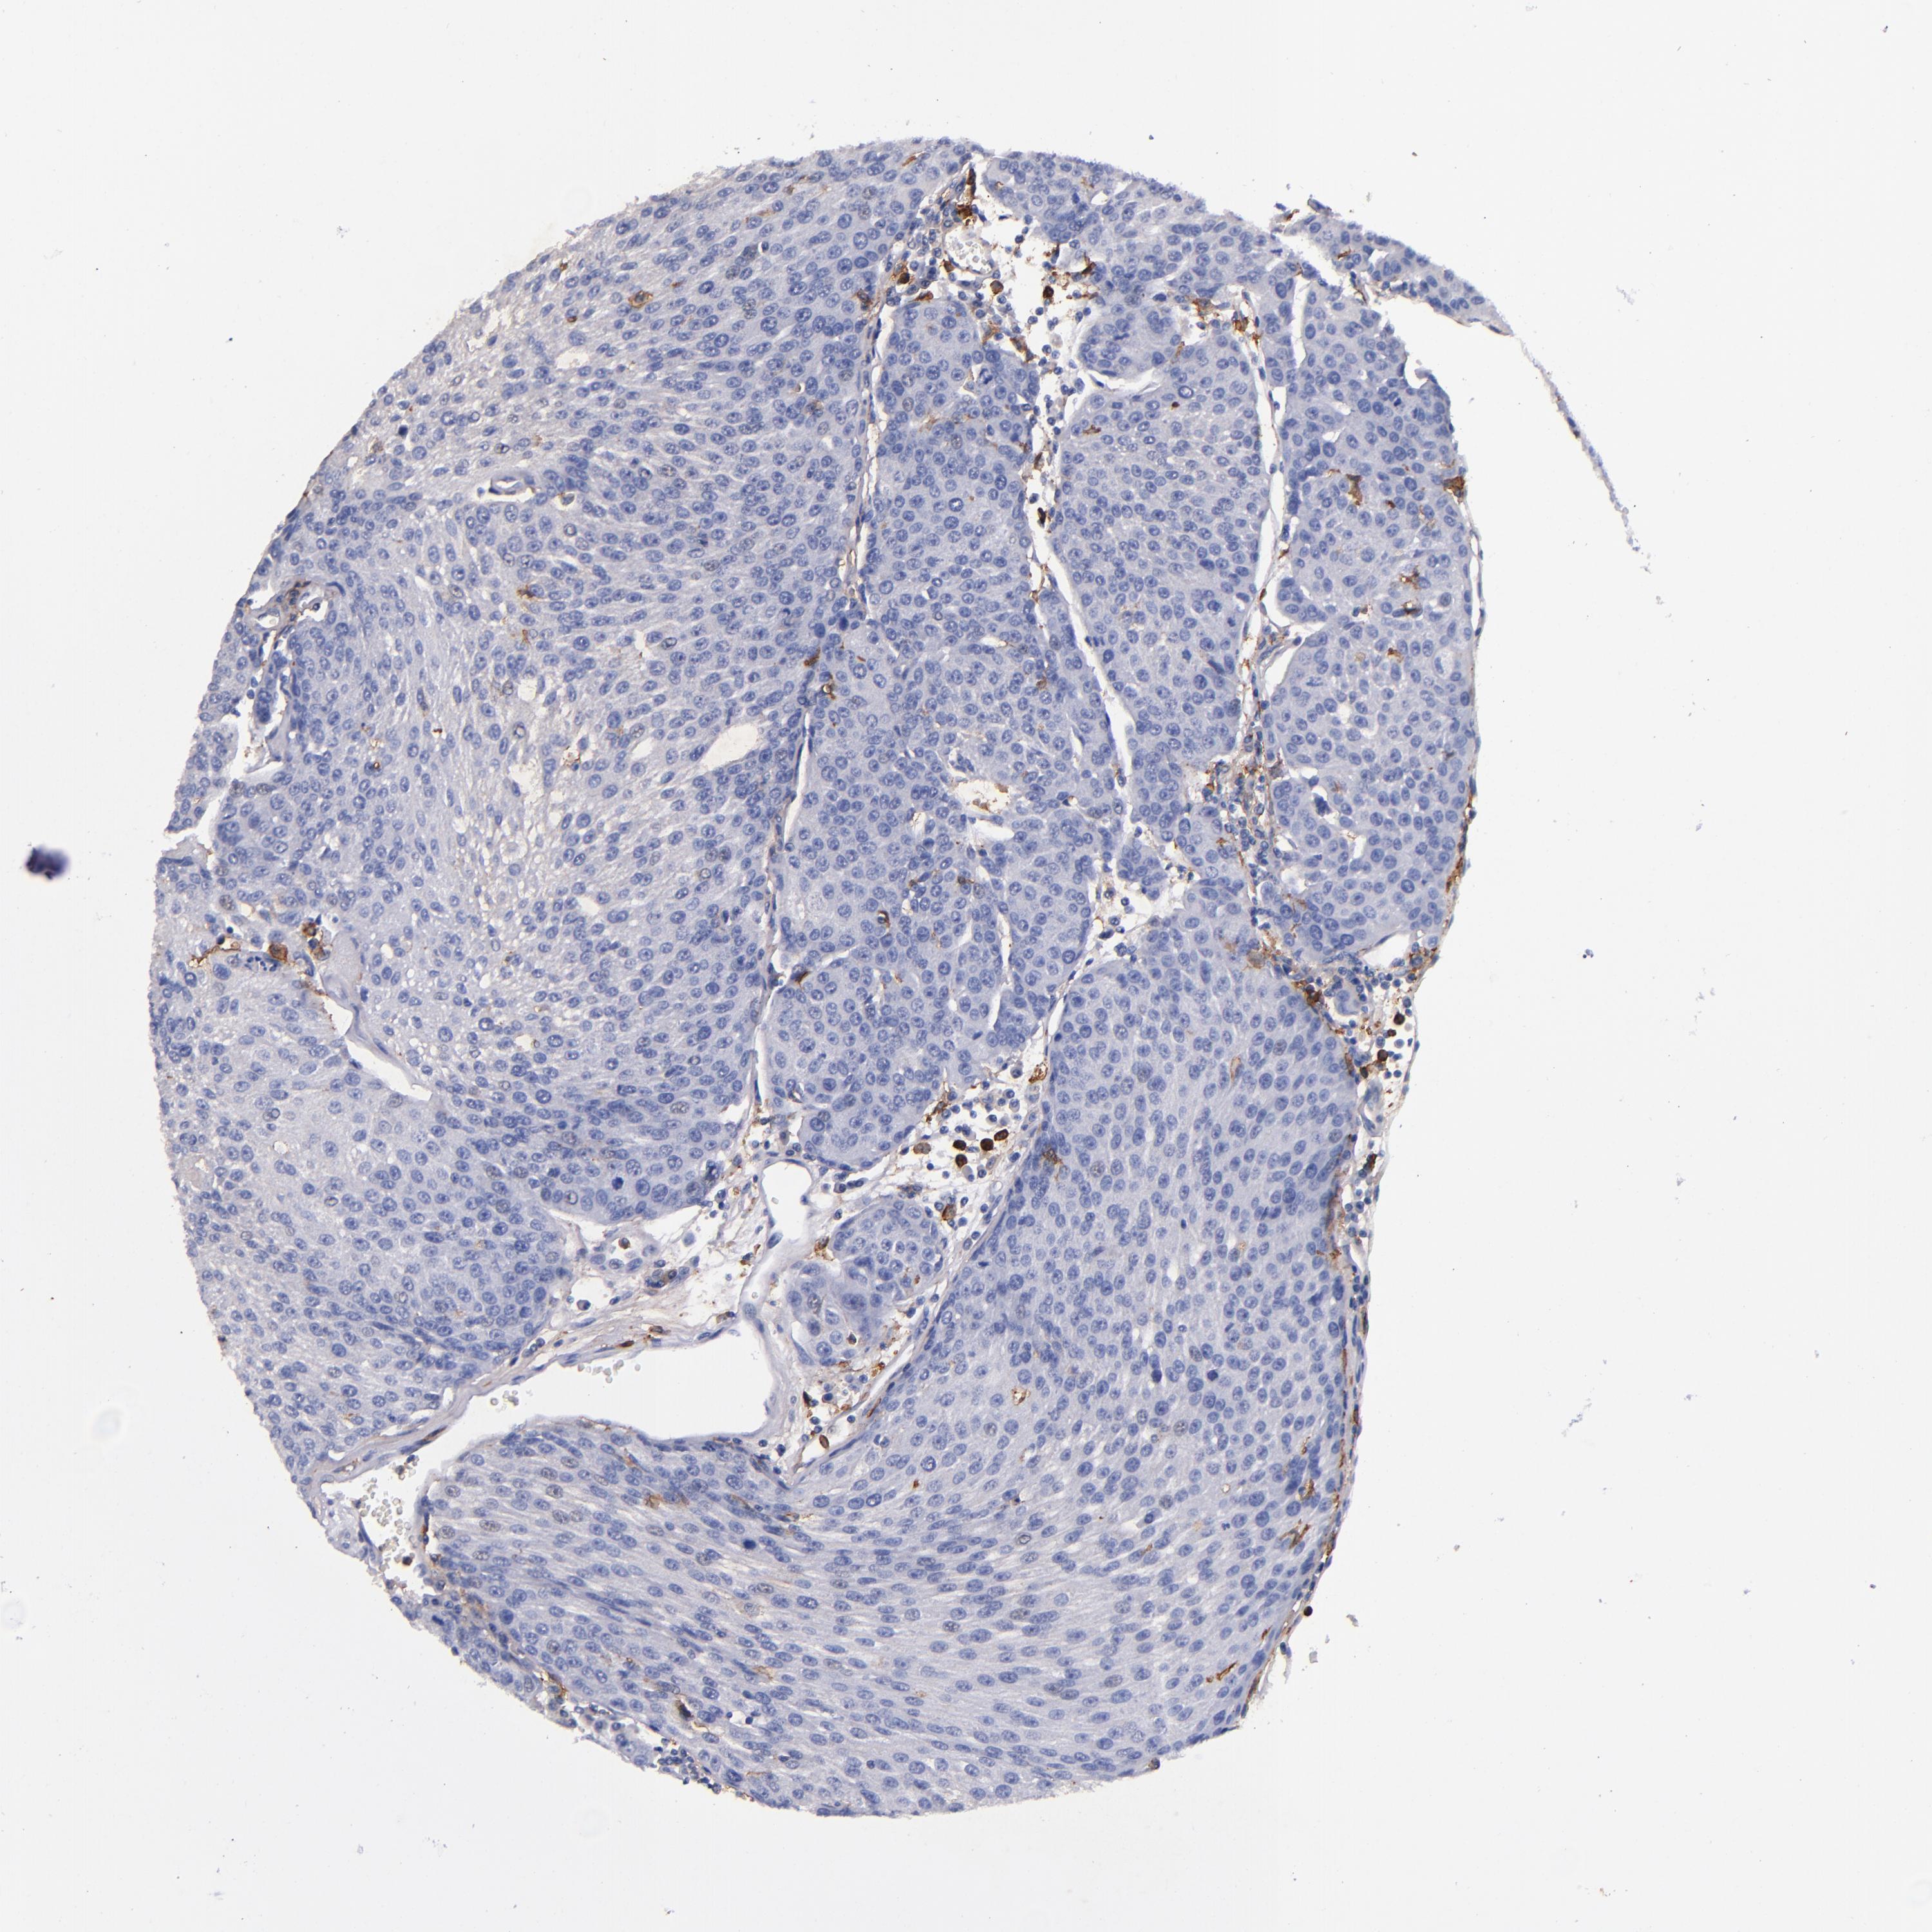

UROTHELIAL CANCER - Protein expressioni

A mouse-over function shows sample information and annotation data. Click on an image to view it in a full screen mode. Samples can be filtered based on level of antibody staining by selecting one or several of the following categories: high, medium, low and not detected. The assay and annotation is described here.

Antibody stainingi

Antibody staining in the annotated cell types in the current human tissue is reported as not detected, low, medium, or high, based on conventional immunohistochemistry profiling in selected tissues. This score is based on the combination of the staining intensity and fraction of stained cells.

Each image is clickable and will lead to virtual microscopy that enables deeper exploration of all samples and also displays staining intensity scores, fraction scores and subcellular localization as well as patient and tissue information for each sample.

Antibody HPA054437

Antibody HPA058511

Antibody CAB002776

Antibody CAB015122

Staining

High

Medium

Low

Not detected

Intensity

Strong

Moderate

Weak

Negative

Quantity

>75%

75%-25%

<25%

None

Location

Nuclear

Cytoplasmic/membranous

Cytoplasmic/membranous,nuclear

Urothelial carcinoma, High grade

Urothelial carcinoma, Low grade

Urothelial carcinoma, NOS